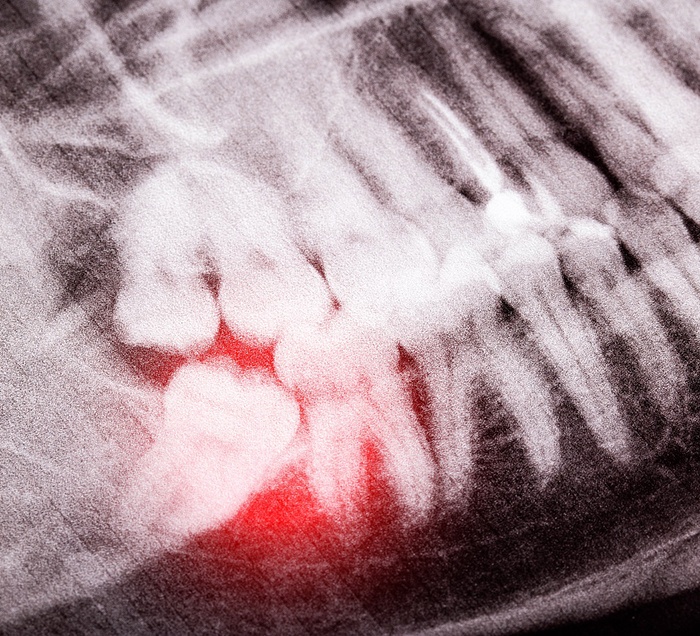

- Impaction

- Persistent pain in the back of the mouth

- A cyst forming near the affected tooth

- An infection that impacts the tooth and the surrounding tissue

- Dental decay forms because of a partially erupted wisdom tooth

- Wisdom tooth eruption causes nearby teeth to shift out of alignment